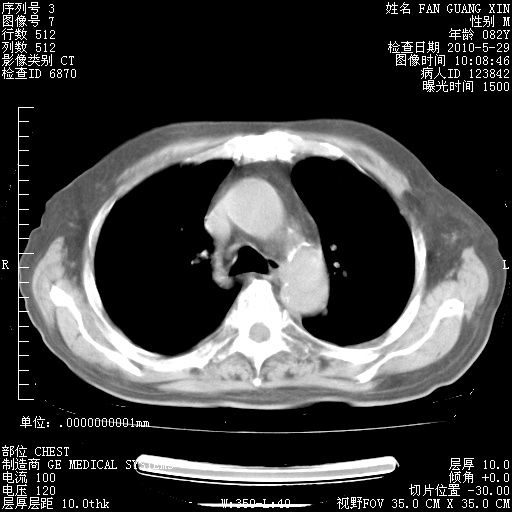

再治疗10天后的肺部CT

阅读此次胸部CT,肺间质渗出性改变较入院时有吸收。目前从体温、白细胞、中性分叶明显增高,肯定存在细菌感染(发生医院感染哦,若无消化道及泌尿系统等感染的依据,肺部感染可能大)。若你院头孢哌酮舒巴坦钠耐药率较高,同意你的方案,若48小时体温仍高,可考虑使用碳青霉稀类抗菌药物,同时可予超声雾化、注意滴数时加大液体量。白蛋白33.30g/L较低哦,需加强营养等支持治疗。